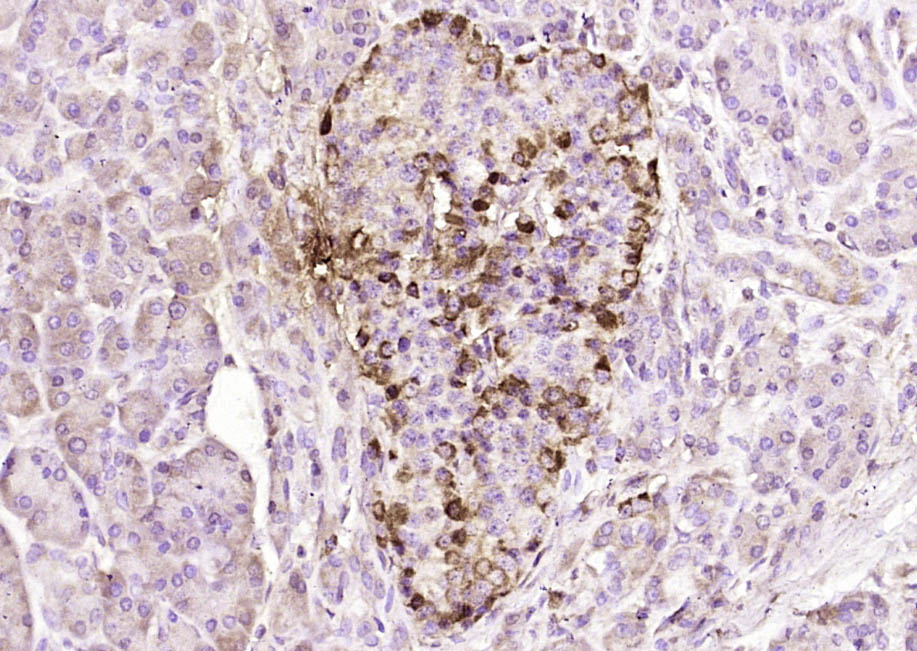

Paraformaldehyde-fixed, paraffin embedded (human gastric carcinoma); Antigen retrieval by boiling in sodium citrate buffer (pH6.0) for 15min; Block endogenous peroxidase by 3% hydrogen peroxide for 20 minutes; Blocking buffer (normal goat serum) at 37°C for 30min; Antibody incubation with (SSTR4) Polyclonal Antibody, Unconjugated (bs-21862R) at 1:200 overnight at 4°C, followed by operating according to SP Kit(Rabbit) (sp-0023) instructionsand DAB staining.